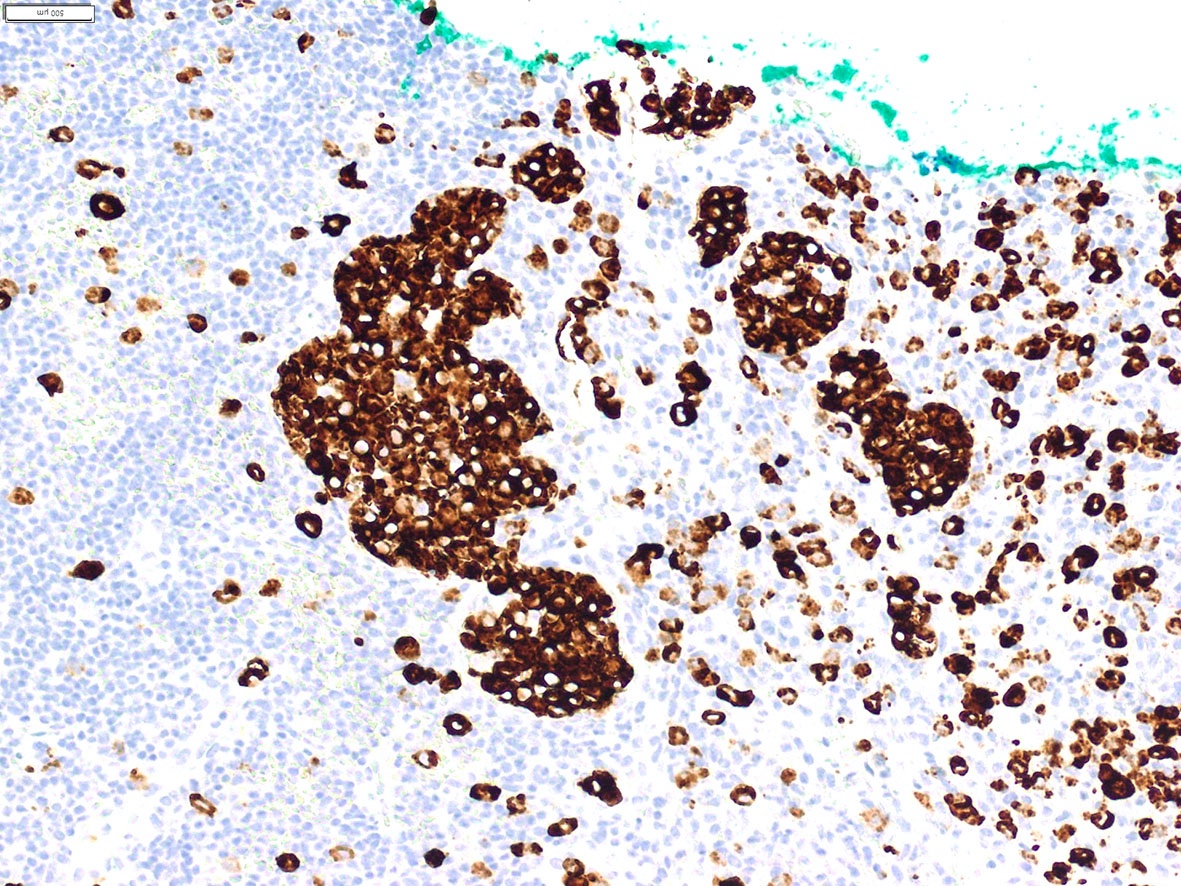

Microscopic (histologic) images

Contributed by A. Cristina Vargas, M.B.B.S., Ph.D., Patricia Guzman, M.D., Fiona Bonar, M.B.B.Ch., Alison Cheah, M.B.B.S. and Martin Jones, M.B.B.S.

Positive staining - disease

- ALK overexpression as a result of gene translocations / fusions:

- ALK+ anaplastic large cell lymphoma (ALCL) (Science 1994;263:1281, Semin Diagn Pathol 2020;37:57)

- Nuclear and cytoplasmic expression: NPM1-ALK and RANBP2-ALK fusions and the ALKATI isoform (Am J Surg Pathol 2017;41:25, Am J Surg Pathol 2011;35:135, Am J Surg Pathol 2016;40:786)